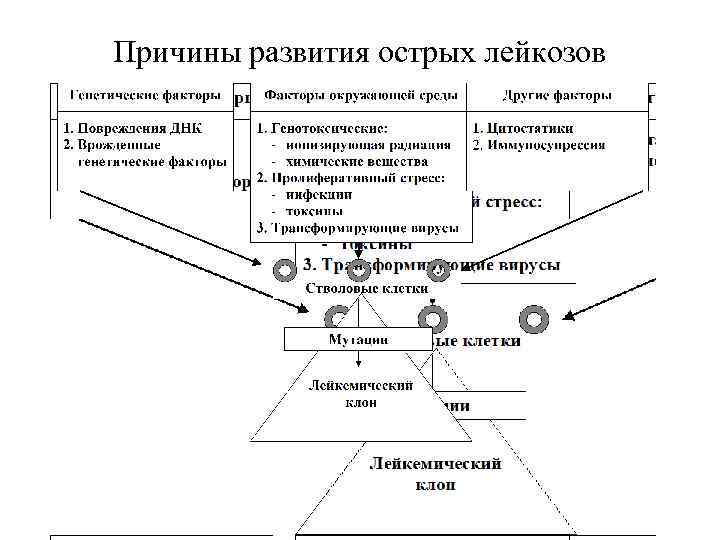

Причины развития острых лейкозов